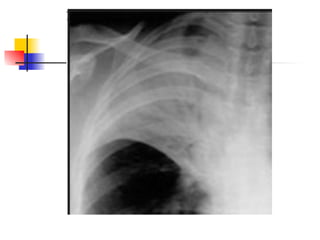

Segmental/alveolar shadows:

In what part of the lung is this located, what radiological signs can you see? Why is the

® hemi diaphragm still clear? Name the lung lobes and segments! What do you see on

a PA and lat CXR when you have consolidation in each of the lobes/ segments